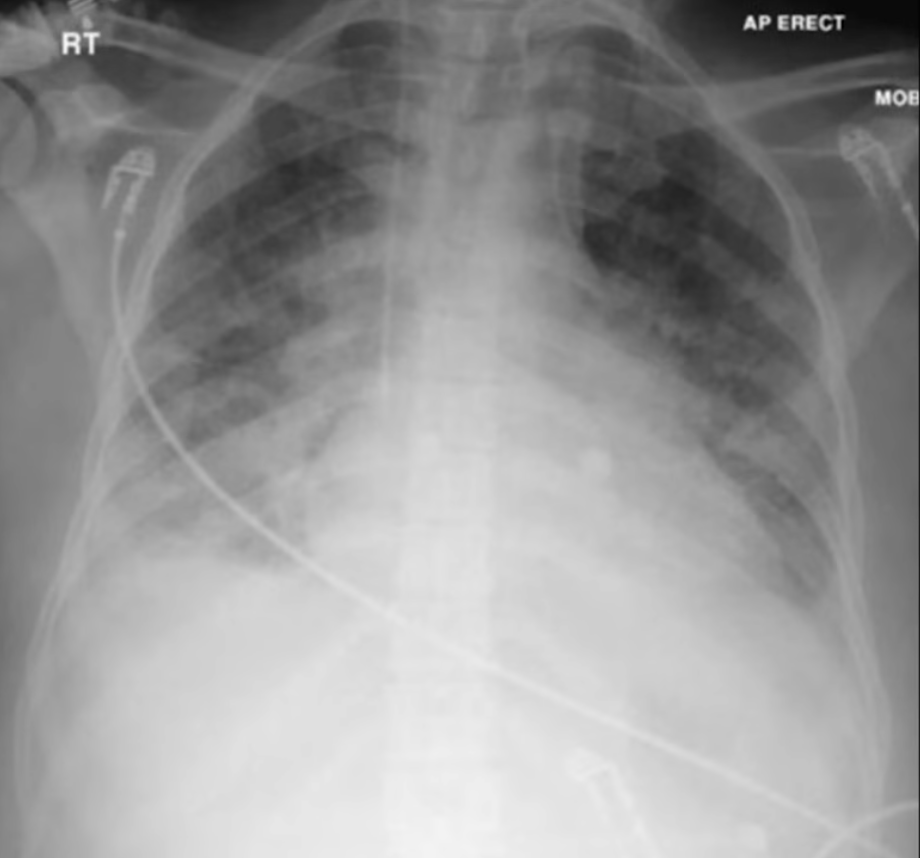

Alveolar (Airspace) Opacities

Due to fluid accumulation within the alveoli and terminal bronchioles; fluid may be oedema, pus, or blood. Opacities are hazy with poorly defined margins but can respect lobar boundaries (unless diffuse).

Differentials are divided into cardiogenic and non-cardiogenic pulmonary oedema (see Acute Pulmonary Oedema). Non-cardiogenic pulmonary oedema defines a spectrum between acute lung injury and acute respiratory distress syndrome.

Differentiation of cardiogenic and non-cardiogenic pulmonary oedema:

Kerley lines

- Kerley A lines are diagonal, unbranching lines 2–6 cm long extending from the hilum, representing channels between peripheral and central lymphatics

- Kerley B lines are faint thin horizontal lines 1–2 cm long at the lung periphery, usually at the bases, representing interlobular septa

Other features: cephalisation (upper lung diversion), bat’s wing pattern